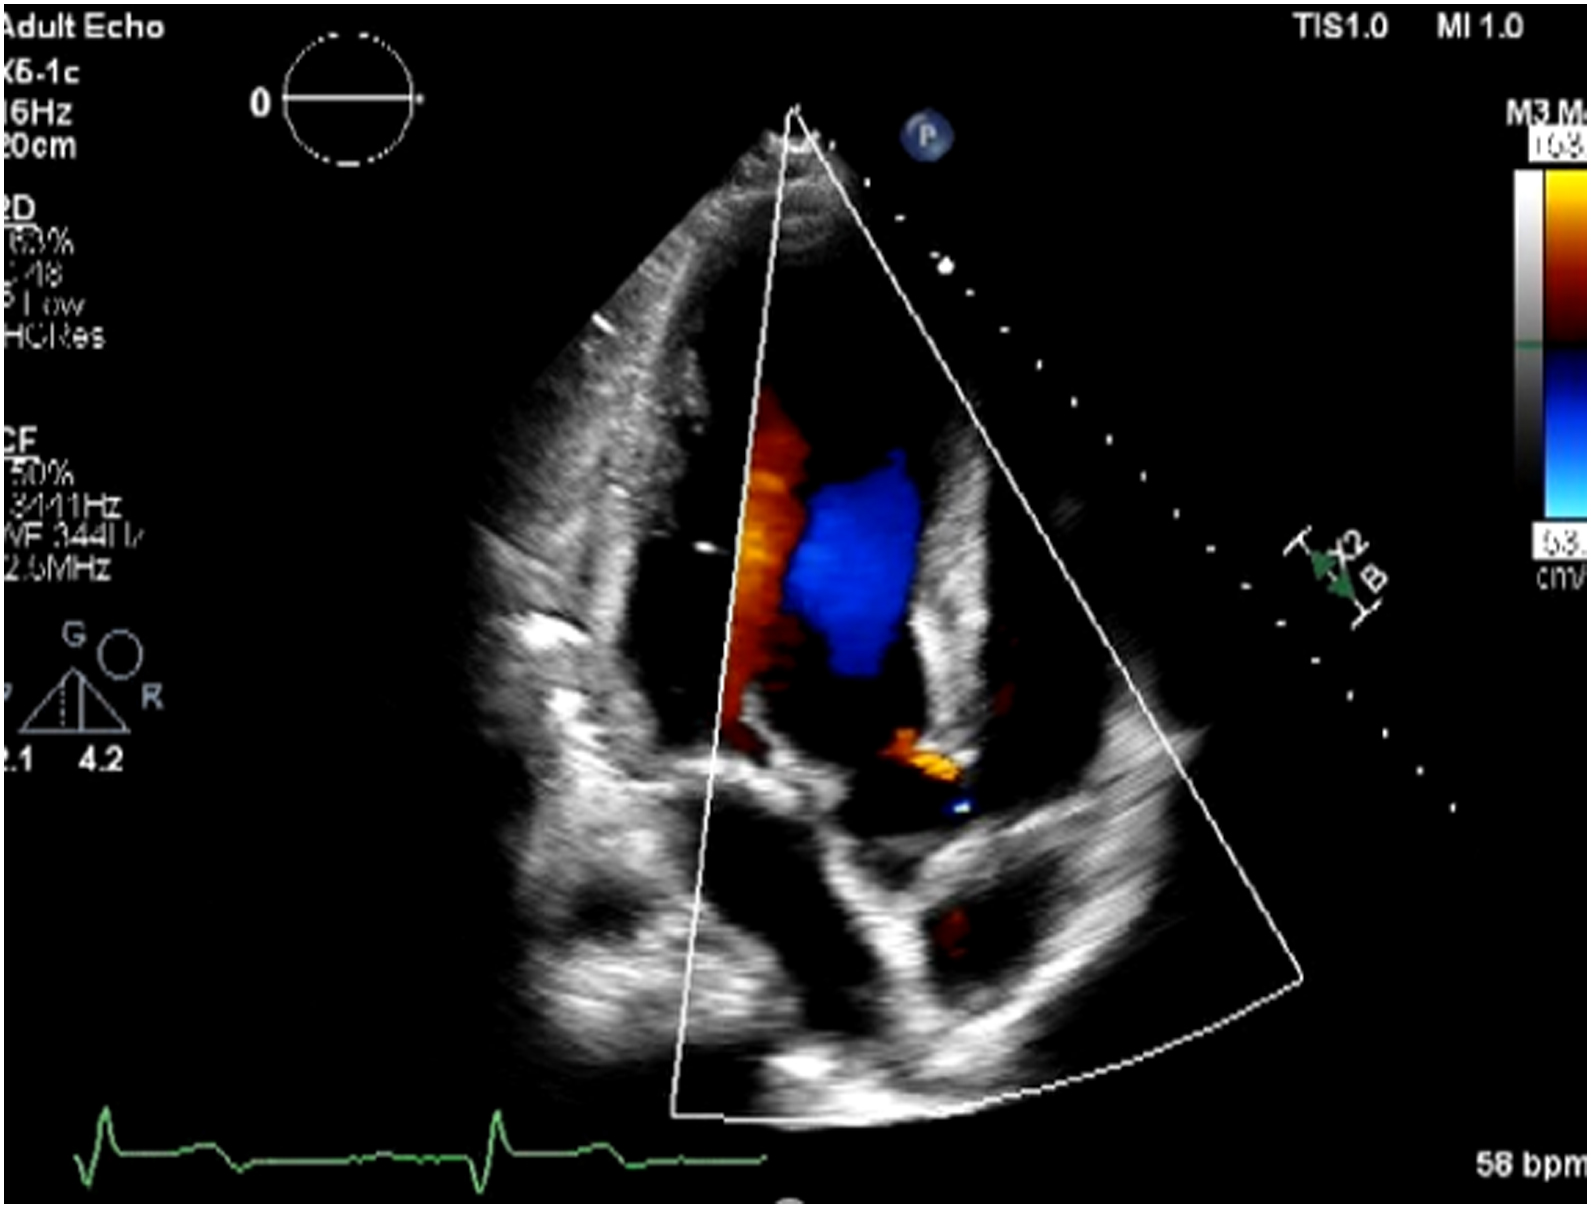

Echocardiogram showed impaired LV systolic function, global wall hypokinesia, normal prosthetic aortic valve function with mild paravalvular leakage and bulging of aortomitral intervalvular fibrosa, suspected

Aortomitral intervalvular fibrosa aneurysm.